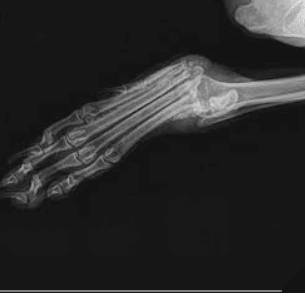

Die liebe Windhund-Mix-Hündin GRACY kam mit einer schweren Beinverletzung und komplett abgemagert ins Shelter. Zur medizinischen Abklärung wurde sie in die Klinik gebracht. Leider sieht es so aus, als könne das Bein nicht gerettet werden, sodass eine Amputation in Betracht gezogen wird. Trotz allem zeigt sie sich unglaublich sanft, kooperativ und geduldig, sie meistert alle Untersuchungen ganz tapfer.